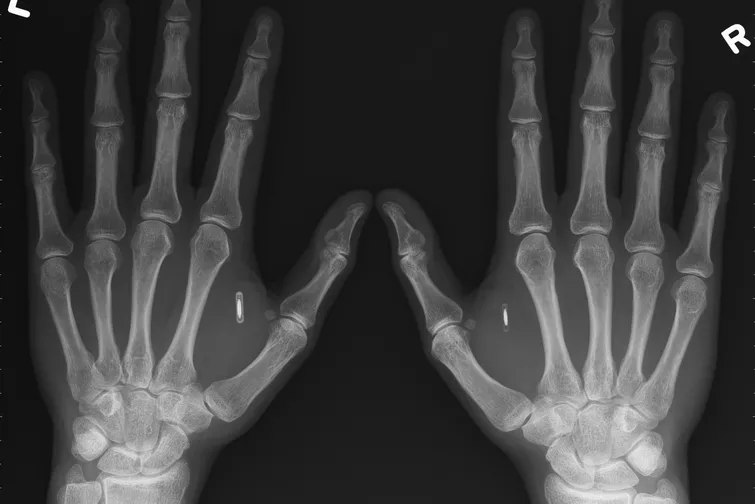

Компания Three Square Market, которая находится в штате Висконсин, введет 50 членам персонала микрочипы под кожу, сообщает телеканал BBC.

Отмечается, что такие меры направлены на то, чтобы упростить доступ людей к электронному оборудованию фирмы. В частности, микрочипы позволят подключаться к компьютерам и пользоваться офисной техникой.

Микросхемы, которые стоят по 300 тысяч долларов, будут вживляться бесплатно.